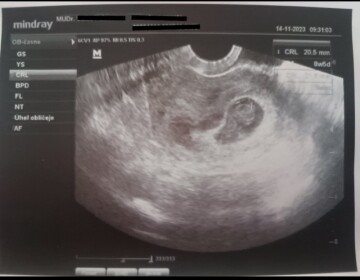

Dobrý den paní doktorko. Jsem 10 týdnů a 6 dní těhotná. Posílám foto z ultrazvuku a mohla byste mi prosím určit, kde leží hematom? Děkuji za odpověď.

Dobrý den, hematom se pravděpodobně nachází na levé straně od plodu, více Vám řekne Váš gynekolog, který Vám vyšetření prováděl a zná i Vaši kliniku, nicméně doporučuji teď klidovější režim - nesportovat, bez pohlavního styku, ideálně užívat progesteron.

Dobrý den paní doktorko, mohla by jste mi poradit... Na ultrazvuku je těhotenství a zároveň prý i hematom . Nevíte,kde se ten hematom na ultrazvuku nachází? Děkuji mnohokrát.

Dobrý den,

kvalita fotky není vysoká, nicméně takto bych řekla, že zmiňovaný hematon je pravděpodobně vlevo. Nejlepší je se na danou věc zeptat gynekologa právě ve chvíli, kdy ultrazvuk provádí a může Vám vše vysvětlit.